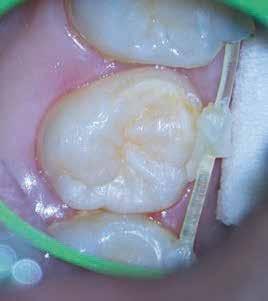

1. a–g. ábrák: A direkt pulpasapkázás lépései. Kiindulási bitewing-felvétel: A meglévő restaurátum közel helyezkedett el a pulpakamrához (a). Kiindulási periapicalis felvétel: Nincs periapicalis elváltozás fennállására utaló jel (b). A pulpaexpozíció (c). A vérzéscsillapítás céljából 20 másodpercen keresztül steril vattagombóccal történő kompressziót követően látható pulpaseb (d). A pulpasapkázás céljából behelyezett anyag, a széli részek tisztázása előtt készült felvétel (e). A röntgenárnyékot nem adó ideiglenes tömés behelyezése után készült felvétel (f). Az első ülés végén a röntgenárnyékot nem adó ideiglenes töméssel ellátott fogról készített röntgenfelvétel (g).

A diagnózisunk reverzibilis pulpitis volt. Periapicalis elváltozás jelenlétét nem vélelmeztük. A fogban lévő amalgámtömés eltávolítása során körülbelül egy 3 mm átmérőjű pulpaseb keletkezett a buccalis pulpaszarvnak megfelelően (1. a–g. ábrák) Mivel nem tapasztaltunk jelentős vérzést, és a diagnózisunk reverzibils pulpitis volt, ezért a direkt pulpasapkázás elvégzése mellett döntöttünk.

A kavitást 2,5%-os nátrium-hipoklorit oldattal fertőtlenítettük, majd sűrű konzisztenciájú kalcium-szilikát alapú anyagot (CeraPutty, Meta Biomed) készítettünk elő a direkt pulpasapkázás elvégzéséhez. Az első kezelés végén röntgenárnyékot nem adó ideiglenes töméssel (NexTemp LC, Meta Biomed) zártuk

az üreget annak érdekében, hogy a direkt pulpasapkázásra használt anyag megfelelő pozícióját radiológiailag ellenőrizni tudjuk. A második ülés során kompozit tömőanyagból (Ezfil, Meta Biomed) direkt adhezív restaurátumot készítettünk.

A kezelést követően a beteg tünetmentes volt. A kérdéses fog a kontrollvizsgálatok során végzett szenzibilitástesztekre fiziológiás reakciókat adott. A hat hónapos kontroll alkalmával készített röntgenfelvételen a sérülésnek megfelelően széles dentinhidat észleltünk (2. ábra). A restaurátum a hároméves kontroll során is megfelelőnek bizonyult (3. ábra)